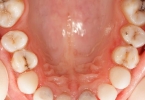

牙床肉发白可能由口腔卫生不良、贫血、口腔扁平苔藓、口腔白斑、真菌感染等原因引起,可通过改善口腔清洁、补充营养、药物治疗等方式缓解。建议及时就医明确病因。

长期吸烟、咀嚼槟榔等刺激导致黏膜角化异常,形成无法擦除的白色斑块,属于癌前病变。早期可通过戒烟和维A酸乳膏治疗,进展期需手术切除配合光动力疗法,术后定期复查防止癌变。

白色念珠菌过度增殖引发口腔黏膜白膜,常见于免疫力低下人群。表现为可剥离的乳白色伪膜,伴口干灼痛。确诊需真菌培养,治疗采用制霉菌素含漱液漱口,重症患者口服氟康唑胶囊,同时控制糖尿病等基础疾病。